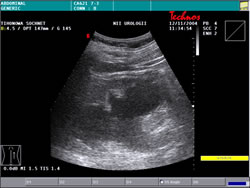

УЗИ: |

|